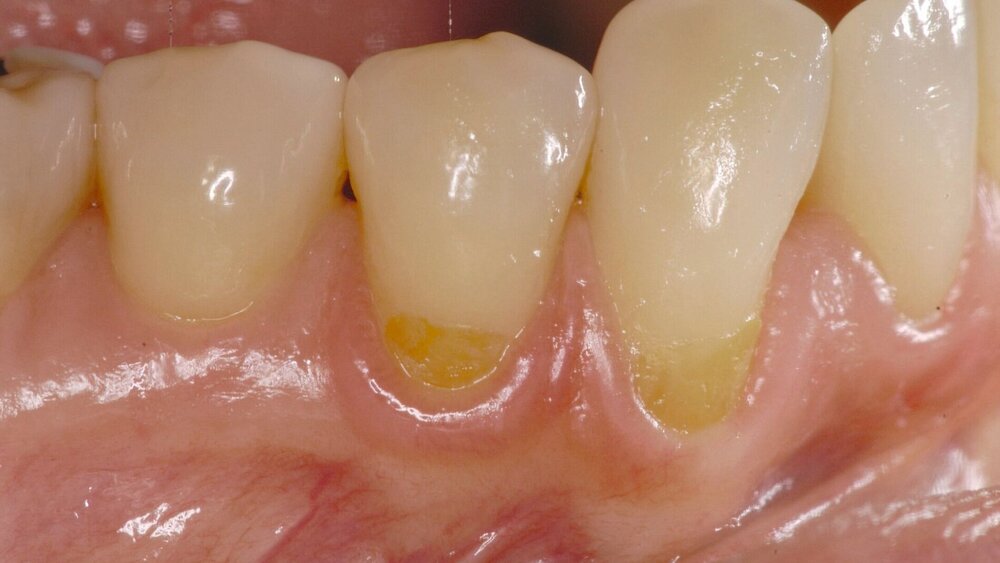

Einfacher Fall und guter Kandidat für eine erfolgreiche chirurgische Rezessionsdeckung: Die Patientin war zum Zeitpunkt der Erstuntersuchung 26 Jahre alt, Hauptanliegen war die Korrektur einer ästhetischen Beeinträchtigung durch die Rezession an Zahn 23. Es bestanden keinerlei Allgemeinerkrankungen oder Allergien. Die Mundhygiene war sehr gut, die Frau Nichtraucherin (Abbildung 3). Die Deckung der Rezession kann hier mit einem koronalen Verschiebelappen, mit lateraler Entlastung und Bindegewebstransplantat oder aber Weichgewebsersatzmaterial erfolgen – mit 100-prozentiger Deckung und gutem Erfolg auch nach fünf Jahren (Abbildung 4). Ein schrittweises Vorgehen zur Rezessionsdeckung ist in Abbildung 5 illustriert.